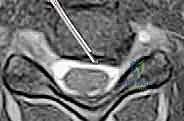

- التصوير بالرنين المغناطيسي (MRI): وهو الفحص الأهم لتحديد موقع الانزلاق الغضروفي بدقة ومدى انضغاط الأعصاب.

الخطوة 3: تحديد مستوى الإصابة بدقة

باستخدام جهاز الأشعة السينية الفلوروسكوبي (Fluoroscopy) داخل غرفة العمليات، يتأكد الدكتور هطيف من الوصول إلى القرص التالف بدقة مليمترية.